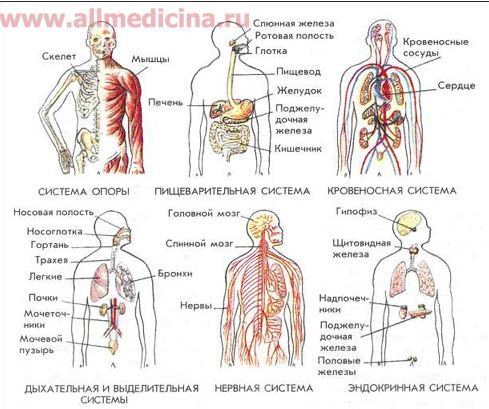

Другой важной частью в организме человека является его наружный покров- кожа. Кожа — наружный покров организма человека, защищающий тело от широкого спектра внешних воздействий, участвующий в дыхании, терморегуляции, обменных и многих других процессах. Кроме того, кожа представляет массивное рецептивное поле различных видов поверхностной чувствительности (боли, давления, температуры и т. д.). Является самым большим человеческим органом, так как кожа полностью покрывает тело человека. Ниже на рисунке представлены различные системы человека, а также из чего они состоят (рисунок представлен с помощью портала allmedicina.ru):

Рис. 2.5. Различные системы человека

На данном рисунке показаны различные важные системы человека с перечислением органов, которые участвуют в процессах этих системах. Читатель должен знать название системы, а также те органы, которые существуют конкретно в этих системах. Сами же системы выполняют разные функции, а именно:

Сами же органы каждой из систем будут рассматриваться подробно при изучении конкретных проблем с теми или иными внутренними органами (например, отравление, внутренние психические расстройства).